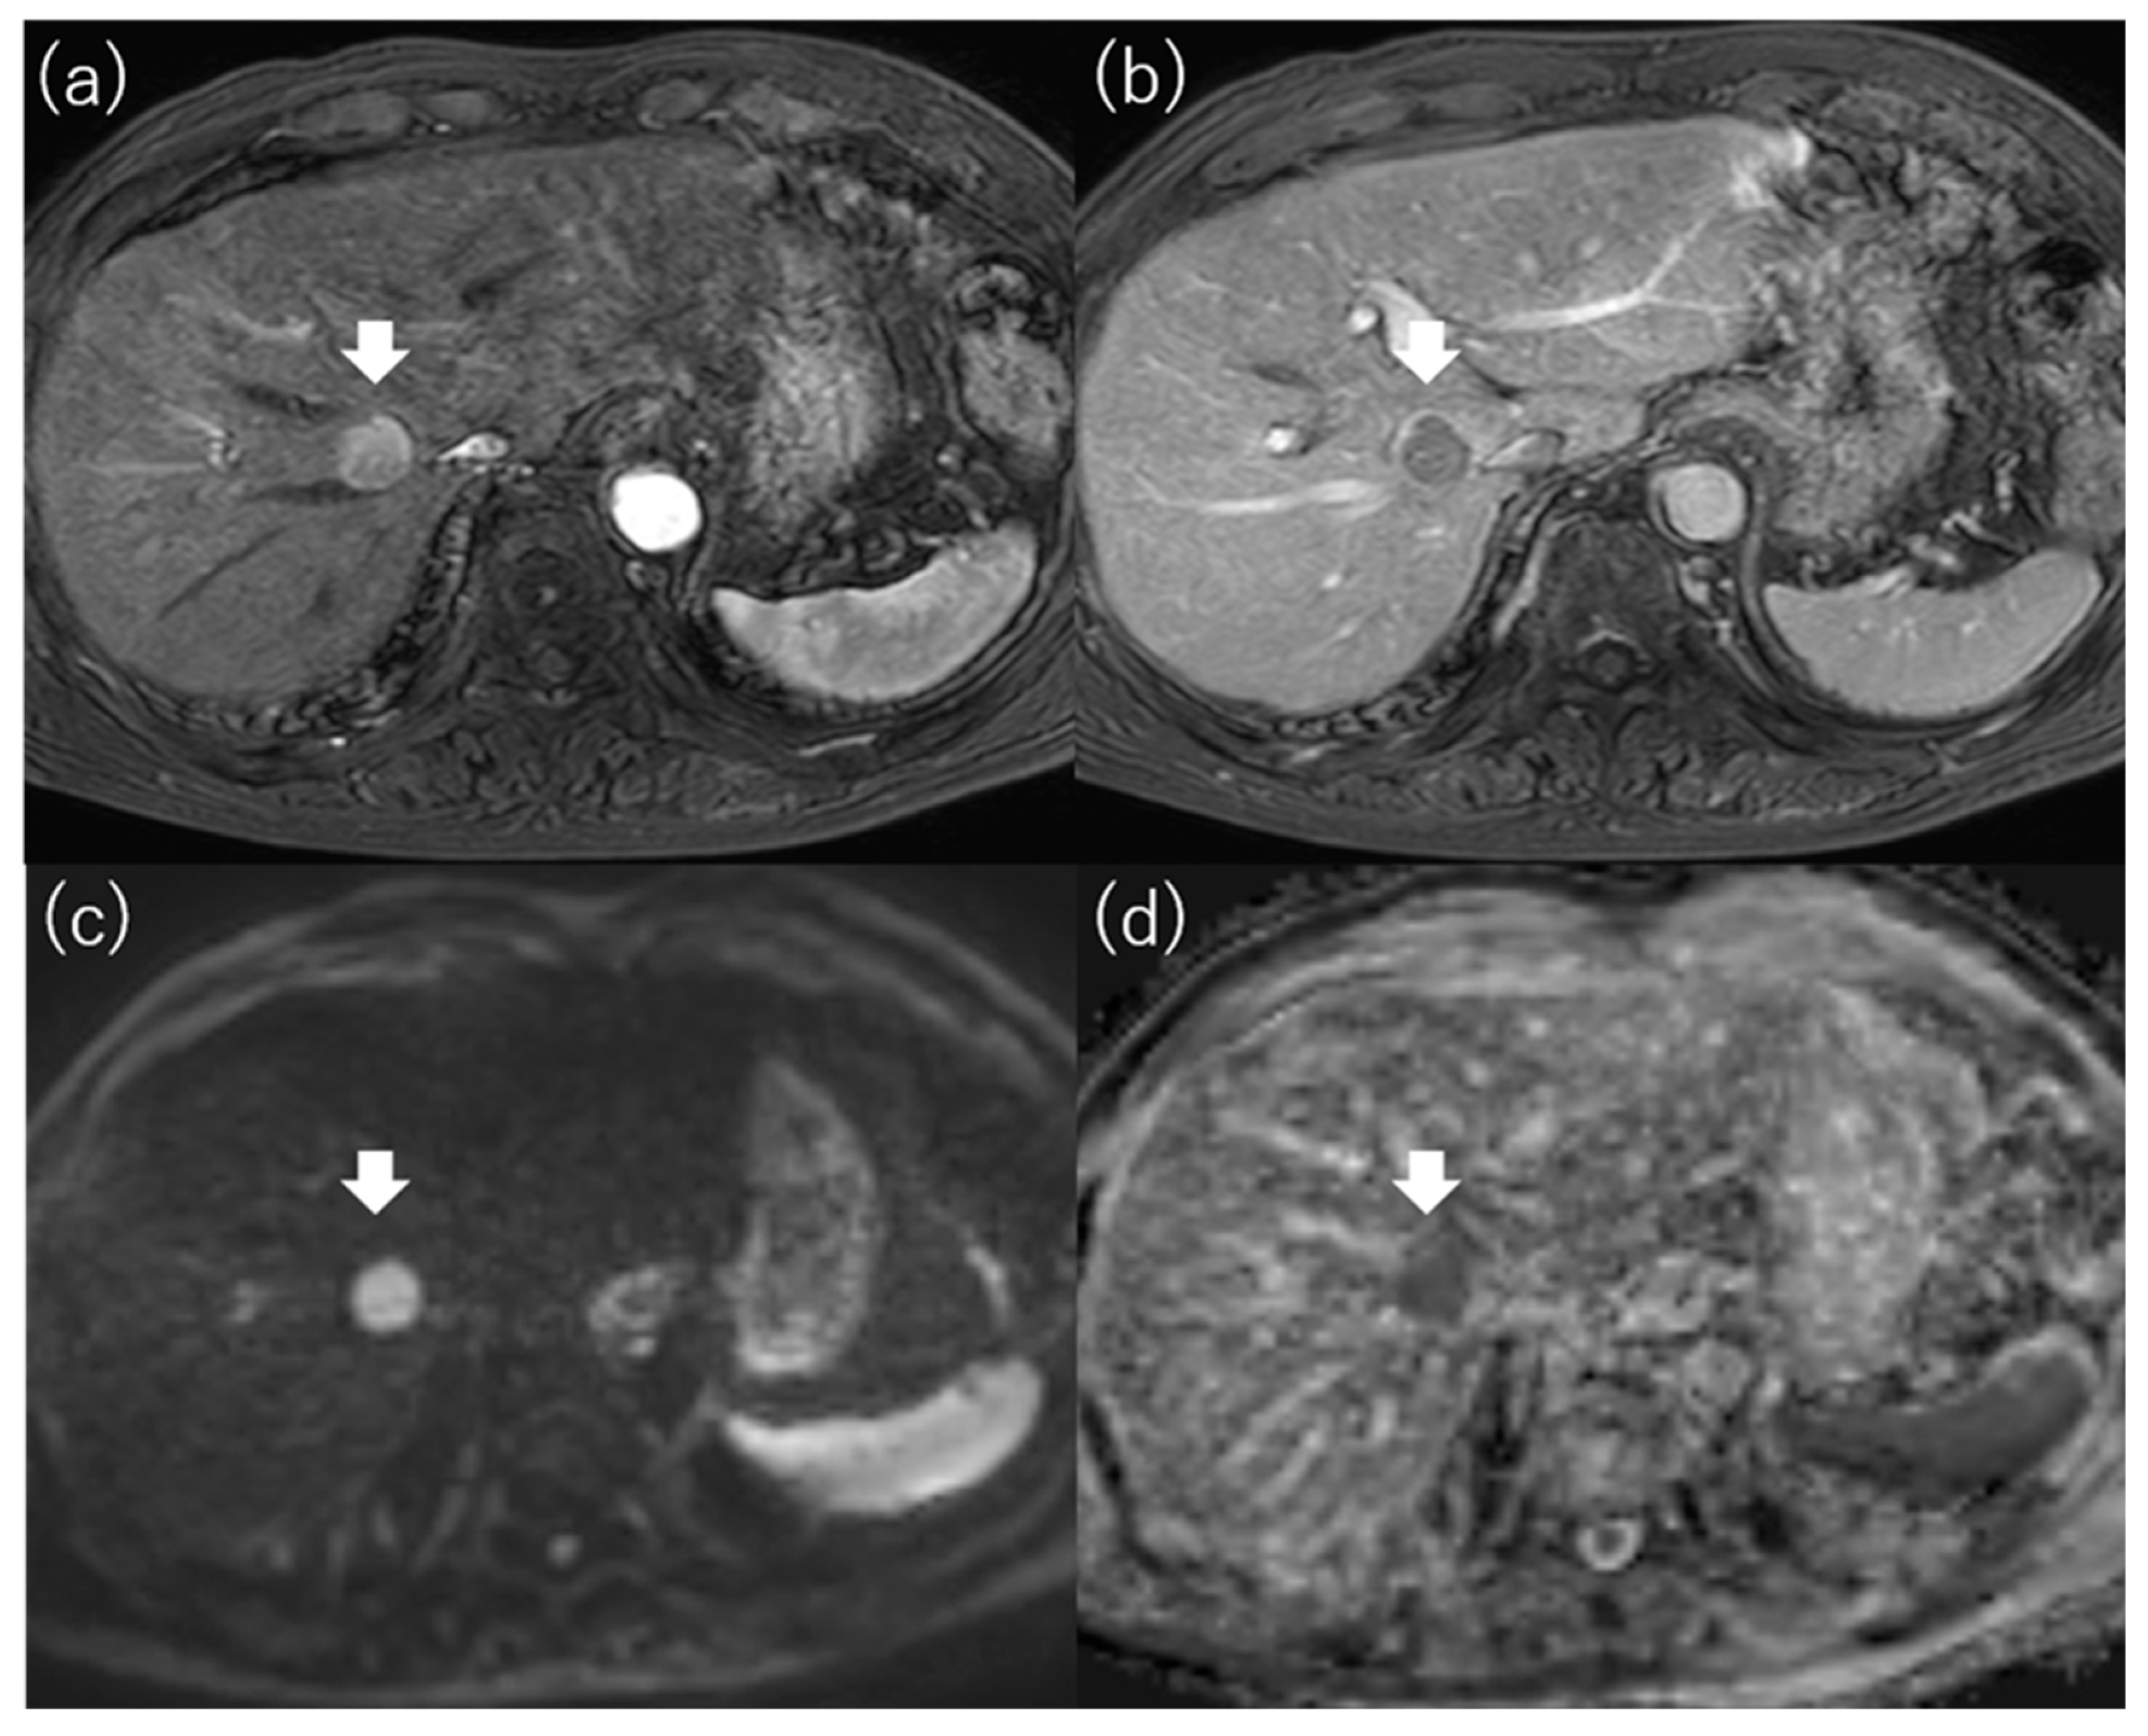

4.1. Enhancement Pattern in the Hepatobiliary Phase

4.2. Enhancement Pattern in the Arterial Phase

4.3. Diffusion-Weighted Imaging

- Lee, S.; Kim, S.H.; Lee, J.E.; Sinn, D.H.; Park, C.K. Preoperative gadoxetic acid-enhanced MRI for predicting microvascular invasion in patients with single hepatocellular carcinoma. J. Hepatol. 2017, 67, 526–534. [Google Scholar] [CrossRef]

- Lee, S.; Kang, T.W.; Song, K.D.; Lee, M.W.; Rhim, H.; Lim, H.K.; Kim, S.Y.; Sinn, D.H.; Kim, J.M.; Kim, K.; et al. Effect of Microvascular Invasion Risk on Early Recurrence of Hepatocellular Carcinoma After Surgery and Radiofrequency Ablation. Ann. Surg. 2021, 273, 564–571. [Google Scholar] [CrossRef]

- Hu, Z.; Yu, N.; Wang, H.; Li, S.; Yan, J.; Zhang, G. Pre-radiofrequency ablation MRI imaging features predict the local tumor progression in hepatocellular carcinoma. Medicine 2020, 99, e23924. [Google Scholar] [CrossRef] [PubMed]

- An, C.; Kim, D.W.; Park, Y.N.; Chung, Y.E.; Rhee, H.; Kim, M.J. Single Hepatocellular Carcinoma: Preoperative MR Imaging to Predict Early Recurrence after Curative Resection. Radiology 2015, 276, 433–443. [Google Scholar] [CrossRef] [PubMed]

- Rhee, H.; An, C.; Kim, H.Y.; Yoo, J.E.; Park, Y.N.; Kim, M.J. Hepatocellular Carcinoma with Irregular Rim-Like Arterial Phase Hyperenhancement: More Aggressive Pathologic Features. Liver Cancer 2019, 8, 24–40. [Google Scholar] [CrossRef]

- Petukhova-Greenstein, A.; Zeevi, T.; Yang, J.; Chai, N.; DiDomenico, P.; Deng, Y.; Ciarleglio, M.; Haider, S.P.; Onyiuke, I.; Malpani, R.; et al. MR Imaging Biomarkers for the Prediction of Outcome after Radiofrequency Ablation of Hepatocellular Carcinoma: Qualitative and Quantitative Assessments of the Liver Imaging Reporting and Data System and Radiomic Features. J. Vasc. Interv. Radiol. JVIR 2022, 33, 814–824.e813. [Google Scholar] [CrossRef]

- Mori, Y.; Tamai, H.; Shingaki, N.; Moribata, K.; Deguchi, H.; Ueda, K.; Inoue, I.; Maekita, T.; Iguchi, M.; Kato, J.; et al. Signal intensity of small hepatocellular carcinoma on apparent diffusion coefficient mapping and outcome after radiofrequency ablation. Hepatol. Res. Off. J. Jpn. Soc. Hepatol. 2015, 45, 75–87. [Google Scholar] [CrossRef]

- Mori, Y.; Tamai, H.; Shingaki, N.; Hayami, S.; Ueno, M.; Maeda, Y.; Moribata, K.; Deguchi, H.; Niwa, T.; Inoue, I.; et al. Hypointense hepatocellular carcinomas on apparent diffusion coefficient mapping: Pathological features and metastatic recurrence after hepatectomy. Hepatol. Res. Off. J. Jpn. Soc. Hepatol. 2016, 46, 634–641. [Google Scholar] [CrossRef]